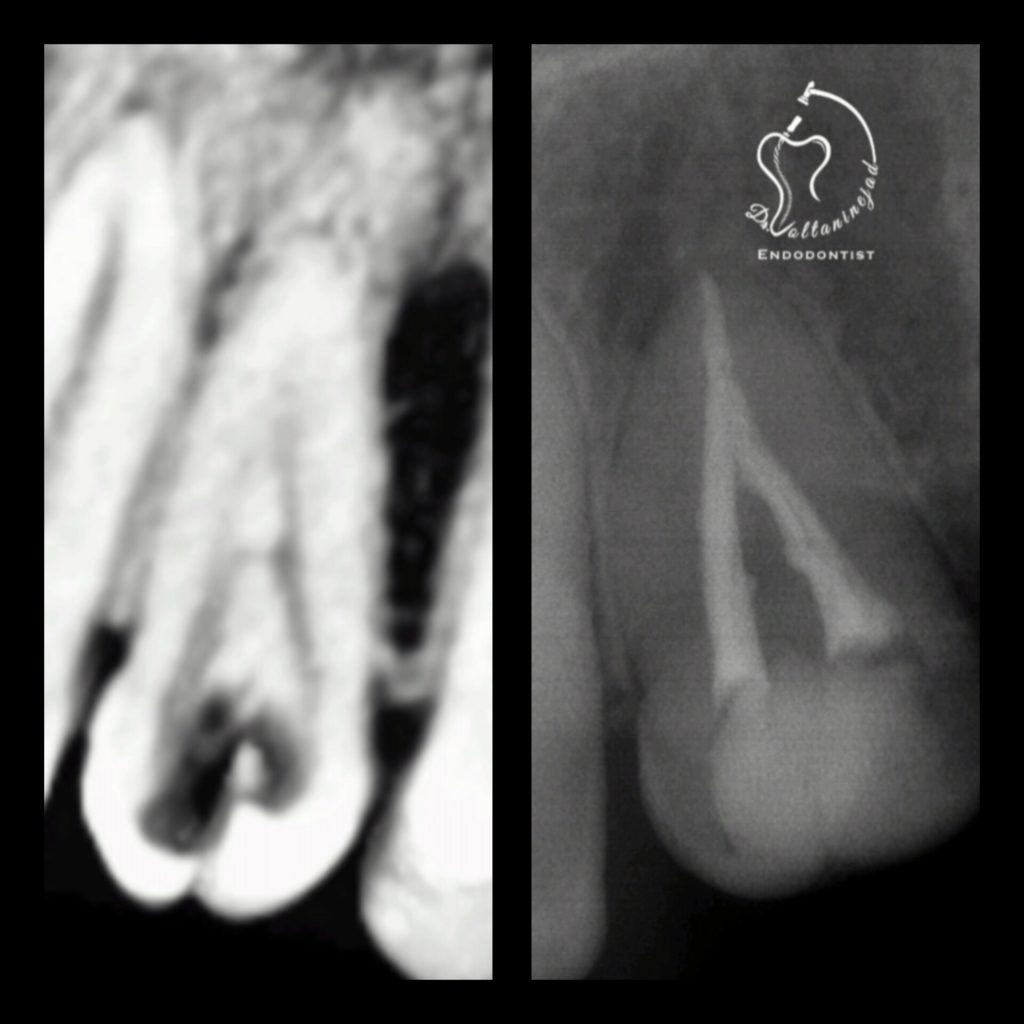

🔹 درمان ریشه دندان کانین با ضایعه وسیع

• شرح کوتاه: بیمار با درد و تورم شدید مراجعه کرد. پس از درمان ریشه تخصصی، ضایعه استخوانی طی ۶ ماه به‌طور کامل بهبود یافت.

• نتیجه: حفظ دندان و بازگشت عملکرد طبیعی.

درمان ریشه دندان کانین